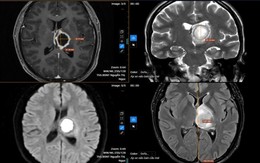

Bệnh nhân không ngờ rằng dù chỉ có những triệu chứng đơn giản, chị lại được chẩn đoán mắc một loại nhiễm trùng nguy hiểm trong não.